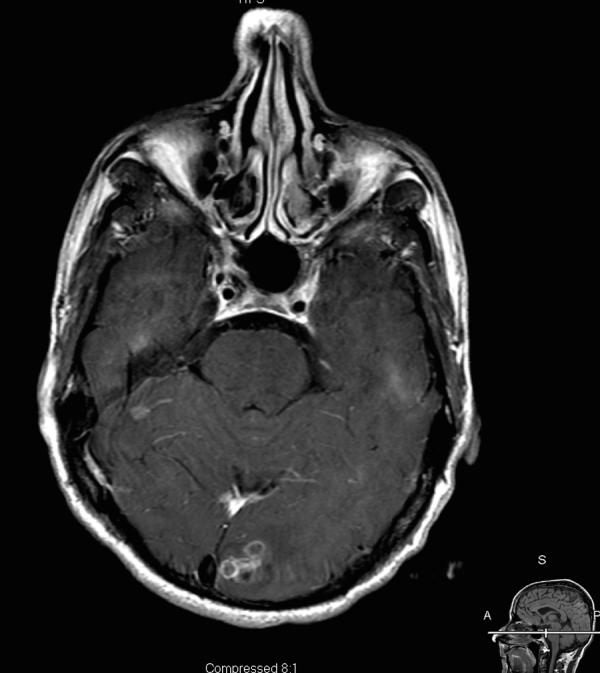

The Mycobacterium avium-intracellulare complex (MAC) is an uncommon cause of brain abscesses even in patients with acquired immunodeficiency syndrome (AIDS). We present a case of a multiple MAC brain abscesses, confirmed by brain biopsy and culture, in a patient with AIDS. The patient's initial symptoms were weakness, confusion and headaches. The patient was initially treated for toxoplasmosis and pyogenic bacterial brain abscesses with no resolution. Following treatment for MAC the patient's abscesses resolved.

鸟分枝杆菌-胞内分枝杆菌复合体(MAC)即使在获得性免疫缺陷综合征(AIDS)患者中,也是脑脓肿的不常见病因。我们报告一例经脑活检和培养确诊为多发性MAC脑脓肿的AIDS患者。患者最初的症状是虚弱、意识模糊和头痛。患者最初接受了弓形虫病和化脓性细菌性脑脓肿的治疗,但病情未缓解。针对MAC进行治疗后,患者的脓肿消退。